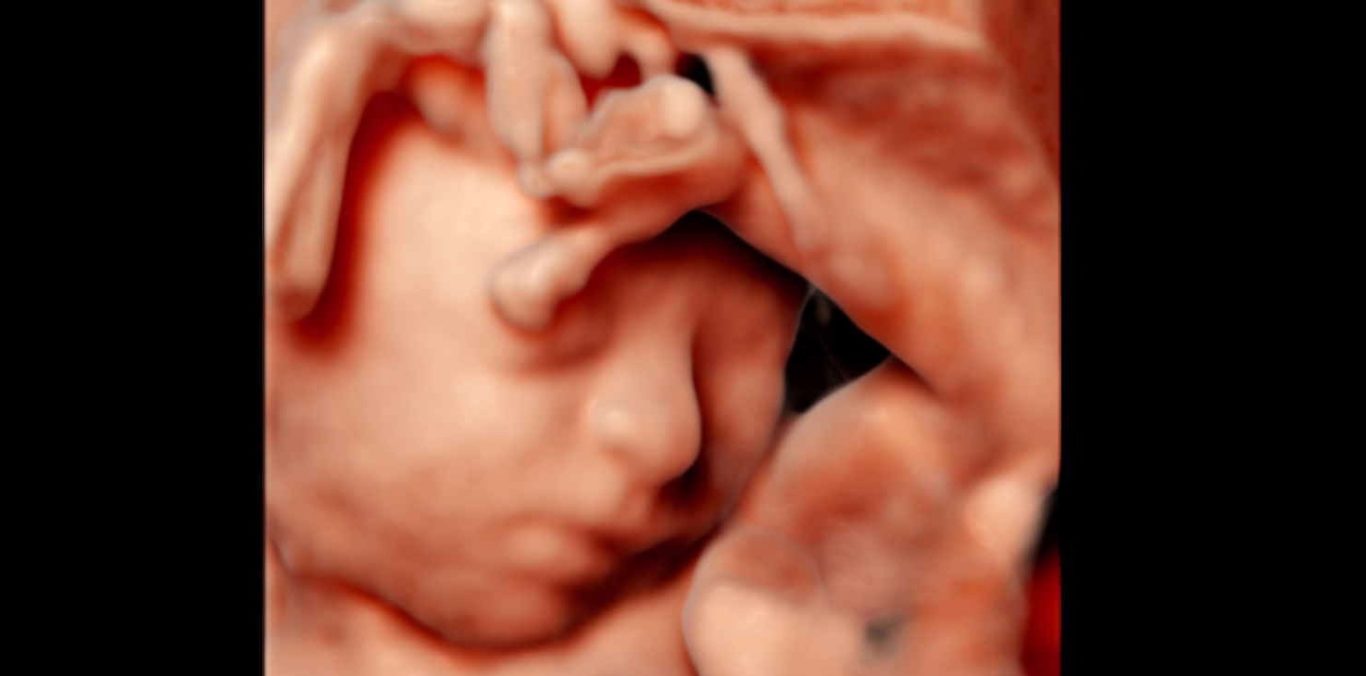

„Feindiagnostik“: 20-24 SSW

Wir schauen Ihr Kind im Ultraschall detailliert von Kopf bis Fuß an. Mit Fortschreiten der Schwangerschaft liegt der Fokus hier besonders auf der Entwicklung von Herz und Kopf Ihres Kindes. So können wir Besonderheiten frühzeitig erkennen, die Schwangerschaft optimal begleiten und die Geburt bestmöglich vorbereiten. In manchen Fällen ist eine Behandlung bereits während der Schwangerschaft möglich.